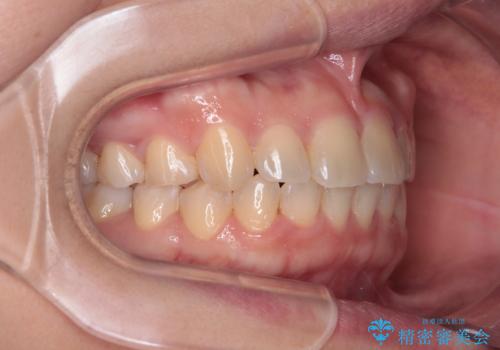

八重歯を治す 非抜歯のワイヤー矯正治療

- 左右の八重歯を気にして来院された患者様です。

ワイヤー装置でもマウスピースでも対応可能な歯列でしたが、マウスピース矯正は自己管理が煩わしいとのことでワイヤー矯正を選択されました。

八重歯である犬歯は歯根が長いため、上顎前歯が出っ歯になるリスクがあるため、必要に応じてアンカースクリューを用いて奥歯を後方に移動させる可能性をお伝えしました。